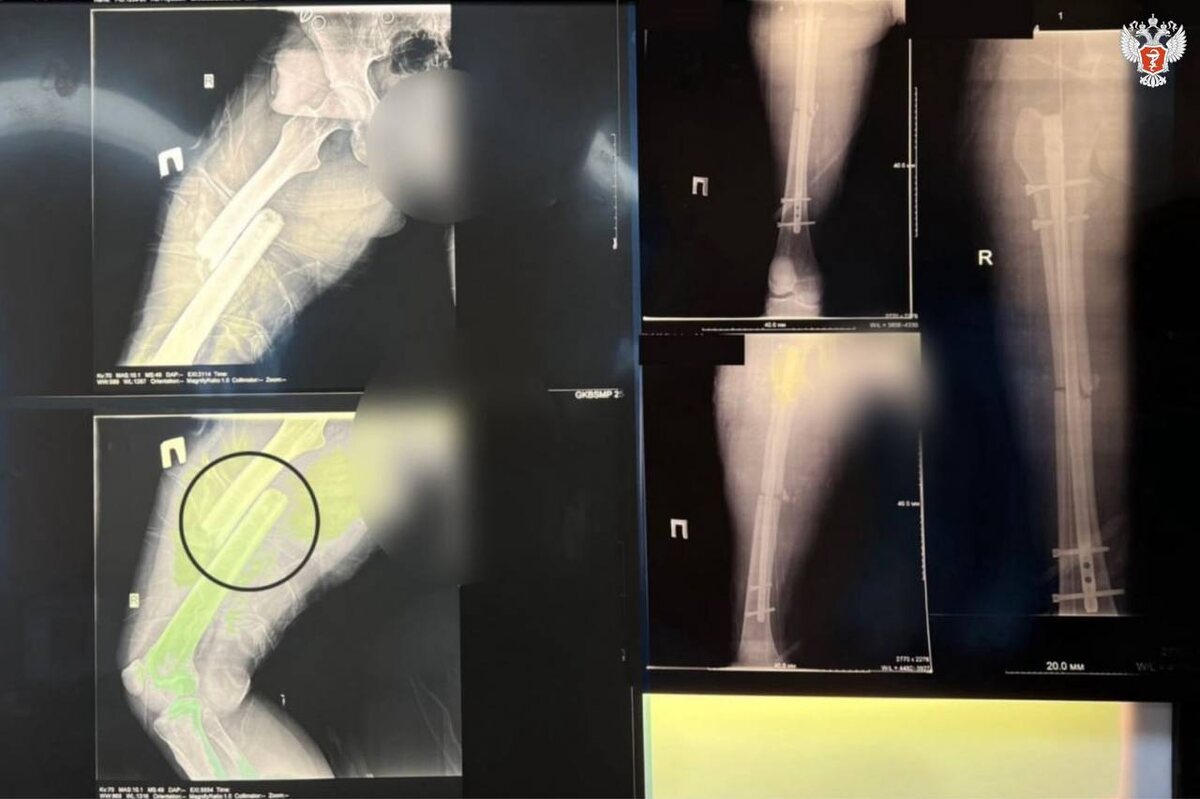

🦴 Спасли после страшной аварии: история пациентки из Волгограда В Волгограде врачи ГКБСМП №25 совершили почти невозможное — спасли 20-летнюю девушку с тяжелейшими травмами после ДТП. 🚑 Пациентка поступила в больницу в состоянии травматического шока. У неё диагностировали: — закрытую черепно-мозговую травму — открытый перелом бедренной кости со смещением — перелом вертлужной впадины (часть тазобедренного сустава) 📉 Перелом бедренной кости опасен не только из-за боли и смещения отломков — он сопровождается обильной кровопотерей до 1,5 литра, что может быть фатально без быстрой помощи. 🛠 Что сделали врачи: — экстренное КТ и УЗИ — хирургическая обработка ран — установка системы скелетного вытяжения — конструкции, которая позволяет постепенно устранить смещение костей. В данном случае отломки бедра были «заехавшими» друг на друга на 11 см — и за несколько дней их удалось развести. 🔩 Через несколько недель провели остеосинтез — операцию по сращиванию костей с помощью штифта и винто

— установка системы скелетного вытяжения — конструкции, которая позволяет постепенно устранить смещение костей. В данном случае отломки бедра были «заехавшими» друг на друга на 11 см — и за несколько дней их удалось развести.

🔩 Через несколько недель провели остеосинтез — операцию по сращиванию костей с помощью штифта и винтов. Использовали малоинвазивную методику: всё сделано через микроразрезы, что минимизирует кровопотерю и ускоряет восстановление.